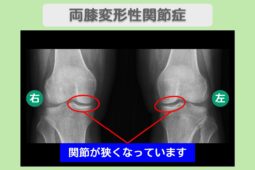

レントゲン所見

レントゲン上では、膝関節の内側が狭くなっており軟骨が減少しています。両股関節の関節が狭くなっておりほぼ末期となっております。